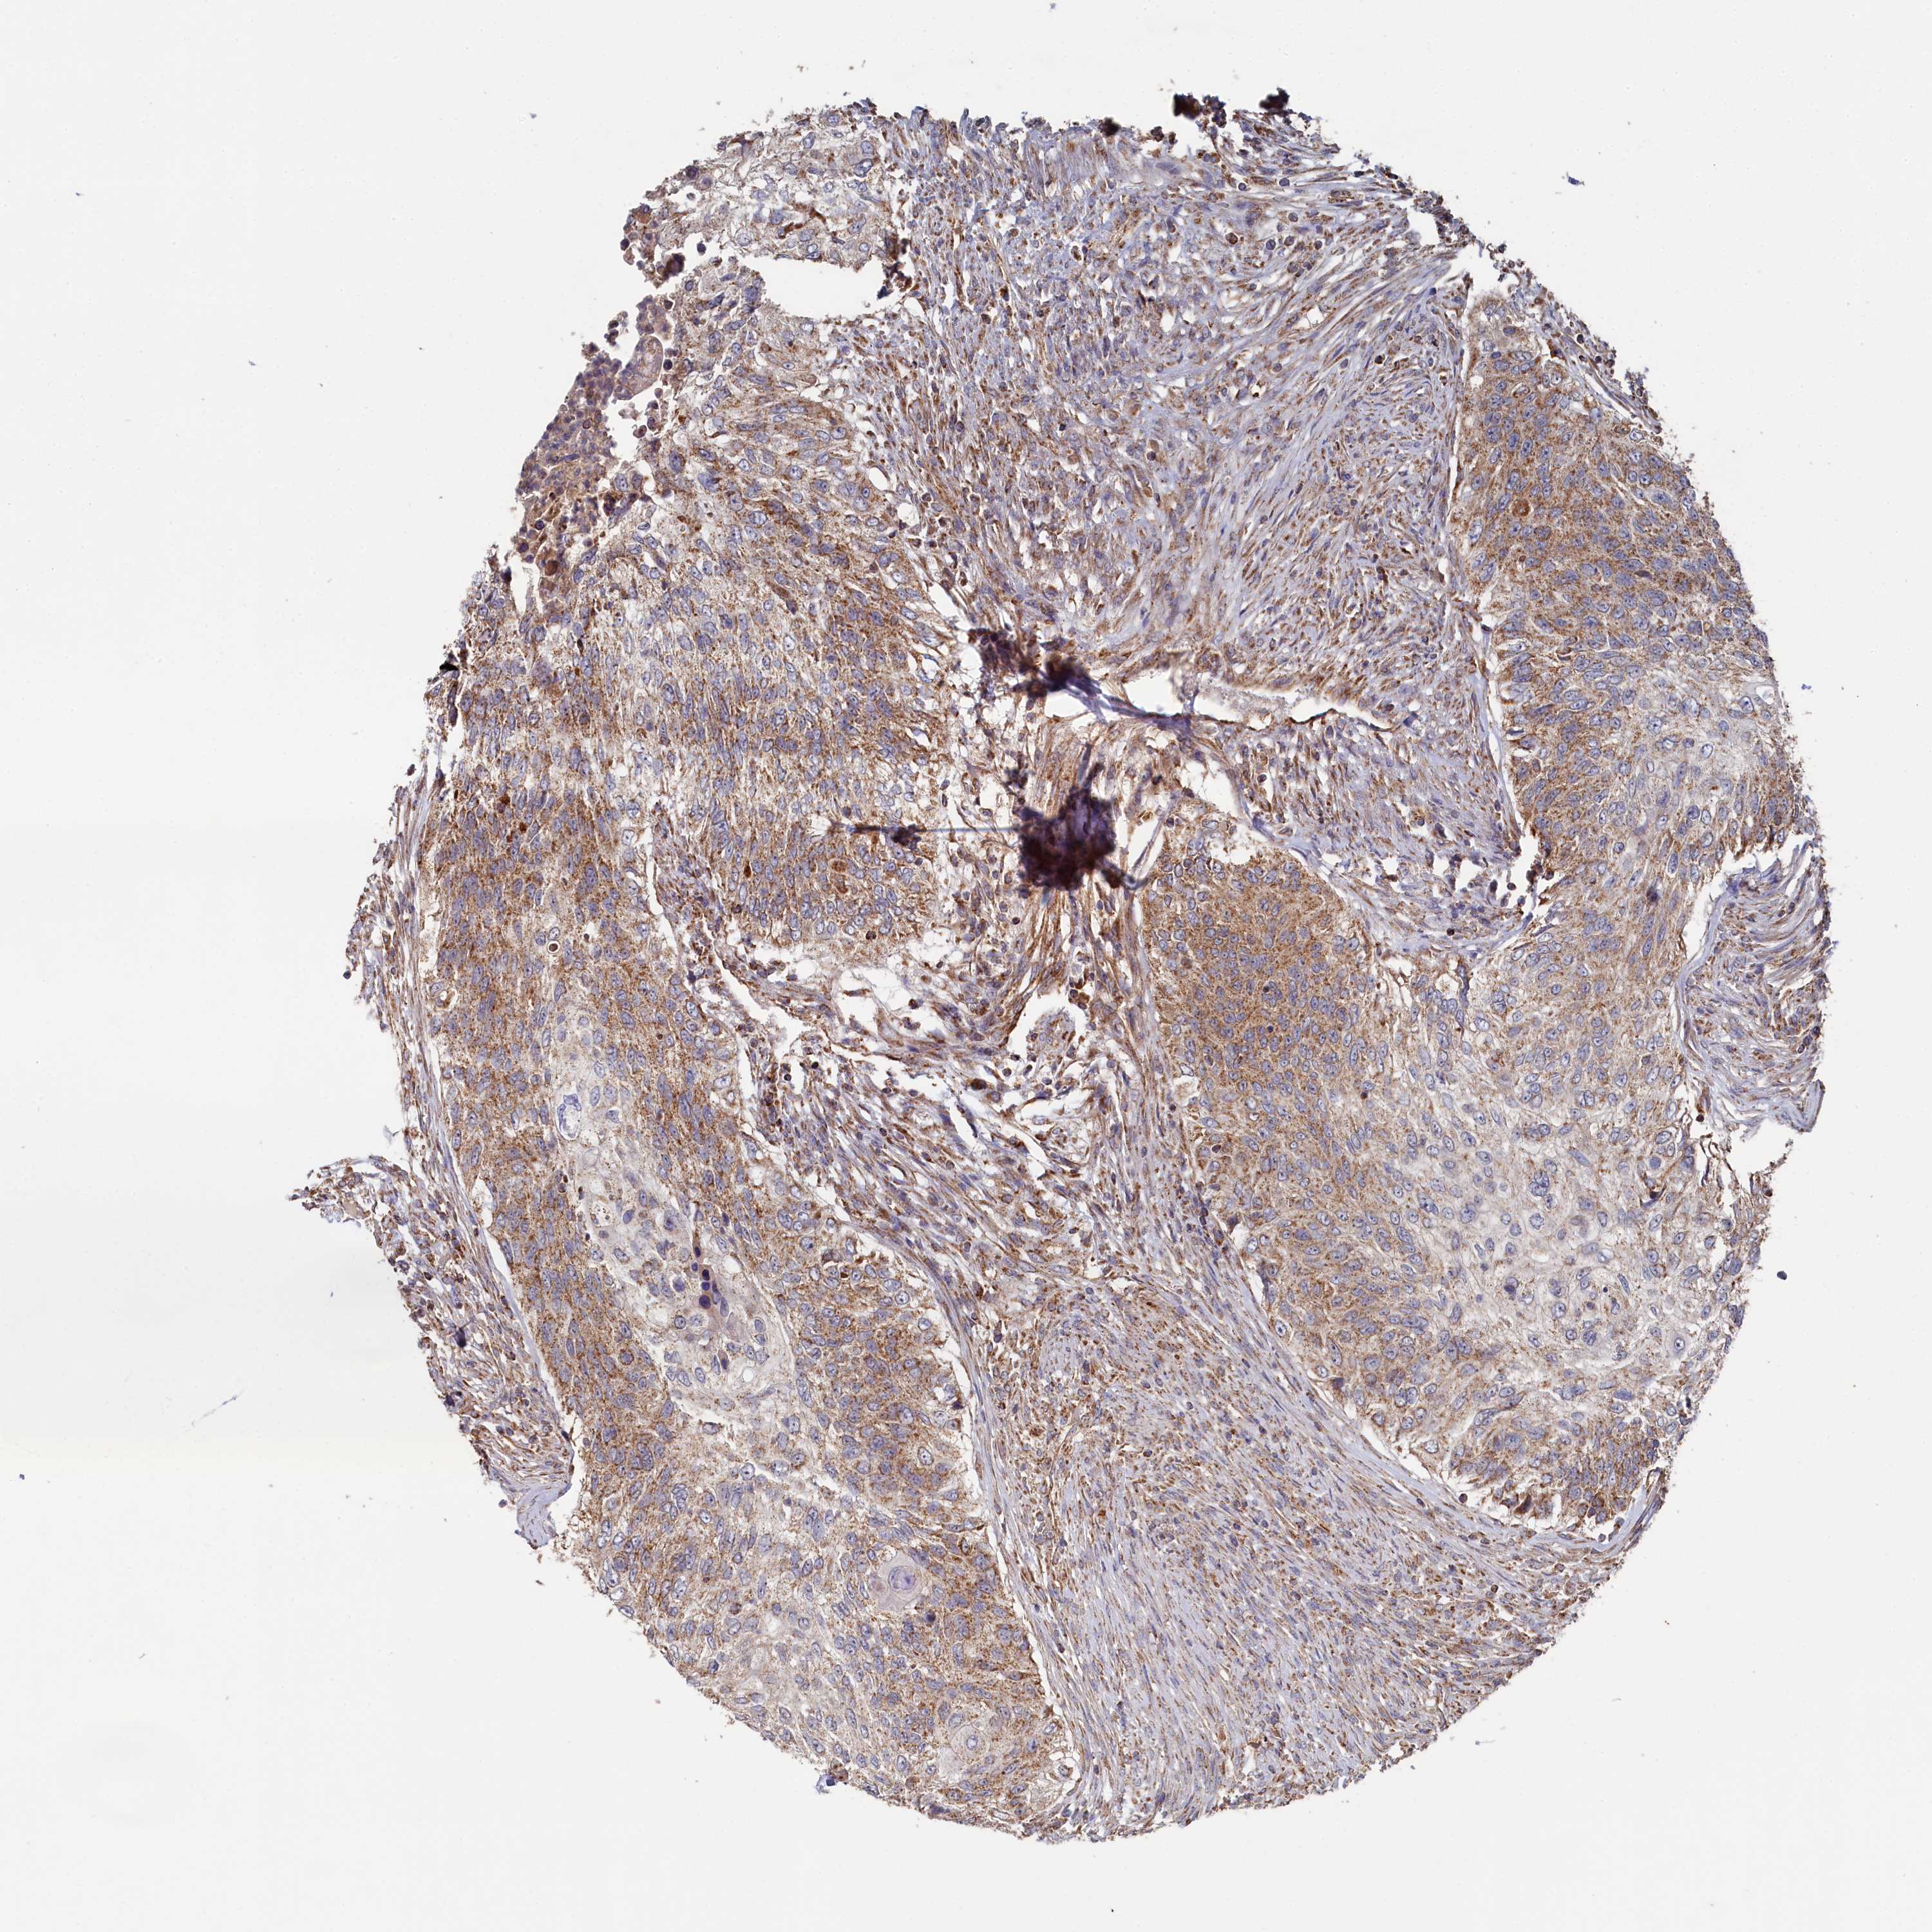

UROTHELIAL CANCER - Protein expressioni

A mouse-over function shows sample information and annotation data. Click on an image to view it in a full screen mode. Samples can be filtered based on level of antibody staining by selecting one or several of the following categories: high, medium, low and not detected. The assay and annotation is described here.

Note that samples used for immunohistochemistry by the Human Protein Atlas do not correspond to samples in the TCGA dataset.

Antibody stainingi

Antibody staining in the annotated cell types in the current human tissue is reported as not detected, low, medium, or high, based on conventional immunohistochemistry profiling in selected tissues. This score is based on the combination of the staining intensity and fraction of stained cells.

Each image is clickable and will lead to virtual microscopy that enables deeper exploration of all samples and also displays staining intensity scores, fraction scores and subcellular localization as well as patient and tissue information for each sample.

Antibody HPA039965

Staining

High

Medium

Low

Not detected

Intensity

Strong

Moderate

Weak

Negative

Quantity

>75%

75%-25%

<25%

None

Location

Nuclear

Cytoplasmic/membranous

Cytoplasmic/membranous,nuclear

Urothelial carcinoma, High grade

Urothelial carcinoma, Low grade